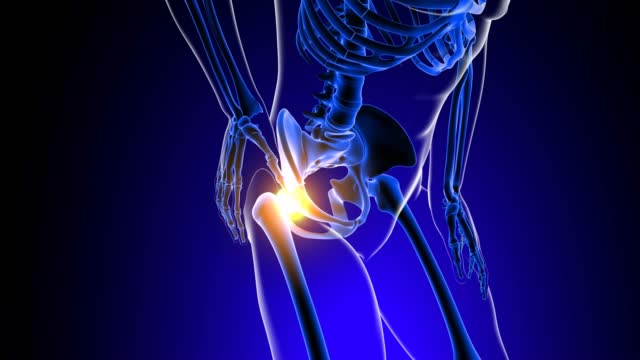

✅고관절 통증 증상 허리디스크? 복합?

이게 고관절이 아프면 단순 통증이라 생각을 하십니다.

단순히 해당 부위에 염증 때문에 발생하는 통증일수도 있습니다.

혹은 허리디스크 때문에 그럴 수도 있습니다. 다양한 복합적인 요인이 있는데요.

고관절 통증의 일반적인 원인 중 하나는 허리디스크입니다. 허리디스크는 허리 부위의 디스크에 문제가 생겨 발생하며, 이로 인해 통증을 겪게 됩니다. 하지만 모든 고관절 통증이 허리디스크로 연결되지는 않습니다. 고관절 주변에도 다양한 원인이 숨어 있을 수 있습니다.

고관절 통증은 종종 단일 원인뿐만 아니라 복합적인 문제에서 비롯됩니다. 이것이 진단과 치료를 어렵게 만들 수 있습니다. 예를 들어, 허리디스크와 함께 관절 주위의 염증, 근육 문제, 혹은 다른 구조적 문제가 동시에 발생할 수 있습니다.